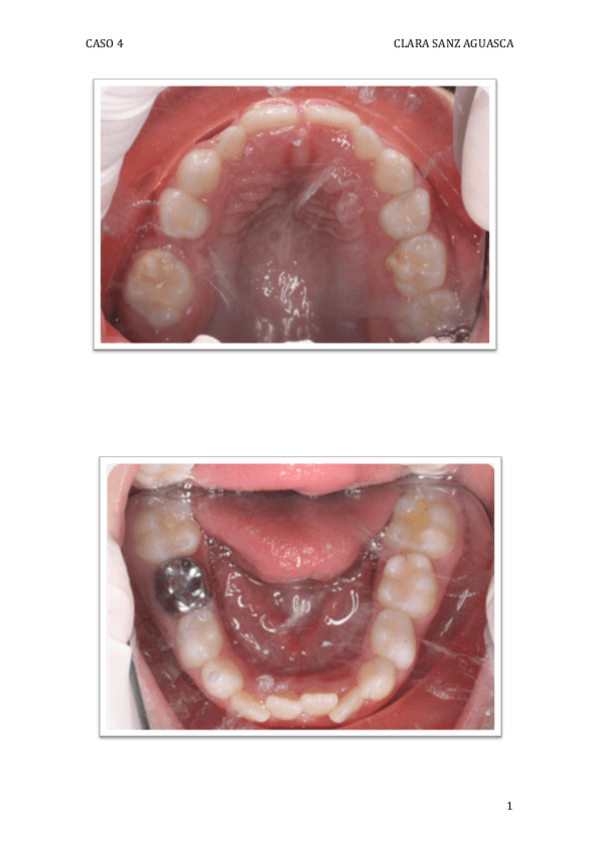

He publicado nuevos apuntes de 4º Odontopediatría: caso-clinico-4.pdf

3 páginas